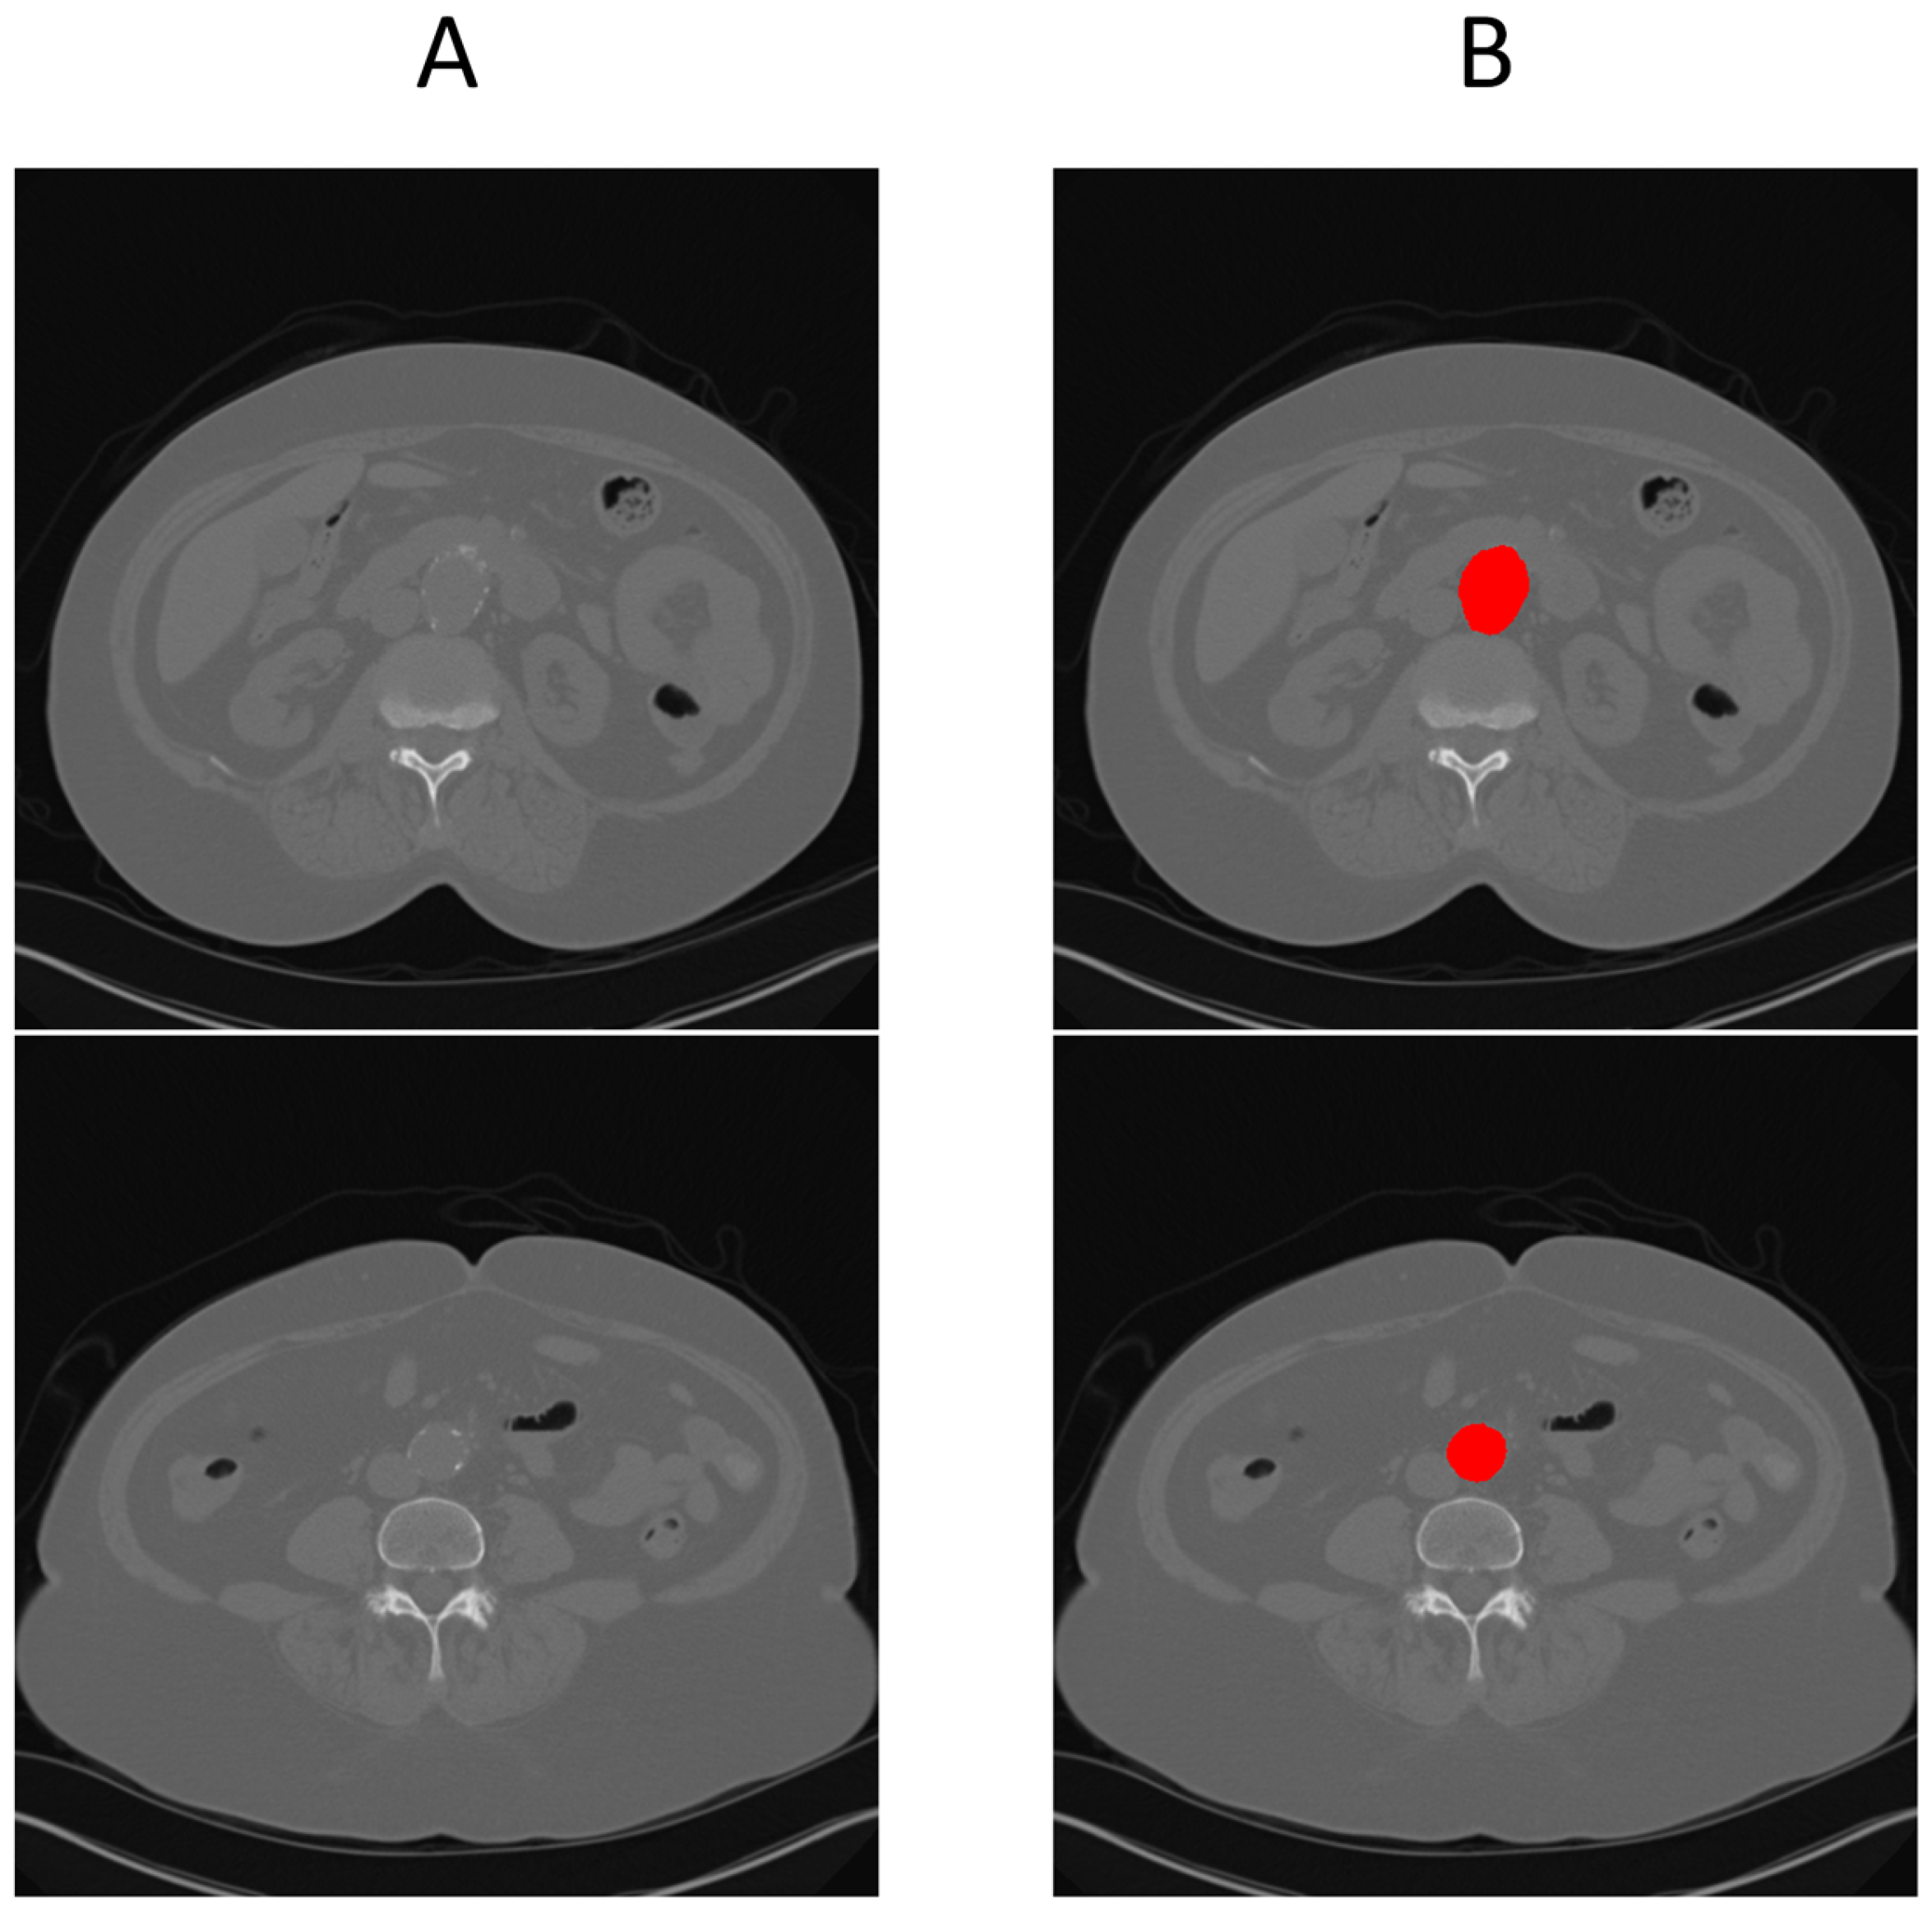

To generate ground truth for aneurysm boundaries, patient scans were manually annotated by an expert in arterial mechanics. The manual annotation process involved identifying the specific slice indices corresponding to the onset and conclusion of the aneurysm, based on morphological changes, primarily variations in cross-sectional diameter, as shown with number 1 and 2 in Figure 1.

Figure 1. Example of the dataset. (A) 3D view front with annotation of the beginning (1) and end (2) of aneurysm. (B) cross-section view of the beginning of the aneurysm. (C) cross-section view of the end of aneurysm.